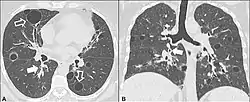

| CT scan of lymphocytic interstitial pneumonia, with pulmonary cysts. | |